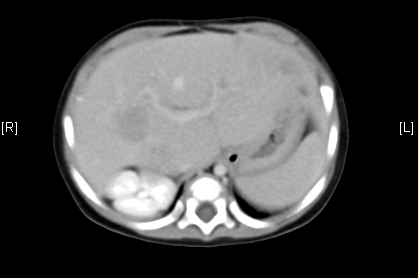

上腹部增强CT:考虑肝母细胞瘤可能性大。

术前CT检查:动脉期